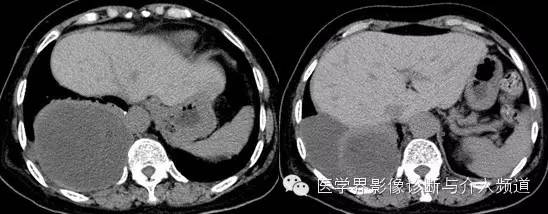

【影像图像】

【影像学表现】

右侧胸腔内见巨大囊性占位,内夹杂少许小片状脂肪及点状钙化灶。内可见分隔。增强动脉期内见血管影走形,静脉期可见病变轻度强化,CT值约为30 Hu,内分隔强化明显。